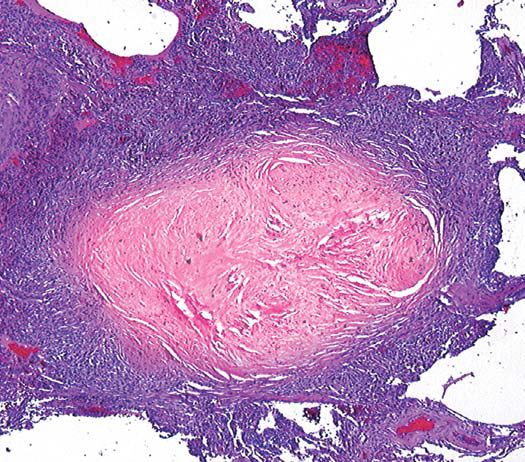

A patient who worked in a quarry for 20 years presents to your clinic for his exam. For some strange reason, a lung biopsy was performed and is shown below. The biopsy shows a concentric whirl of dense, sparsely cellular collagen. The patient has enlarged calcific hilar nodes but he showed no respiratory Syx. What is the Dx? What is another name for the calcific hilar lymph nodes?

Simple nodular silicosis; Eggshell calcification